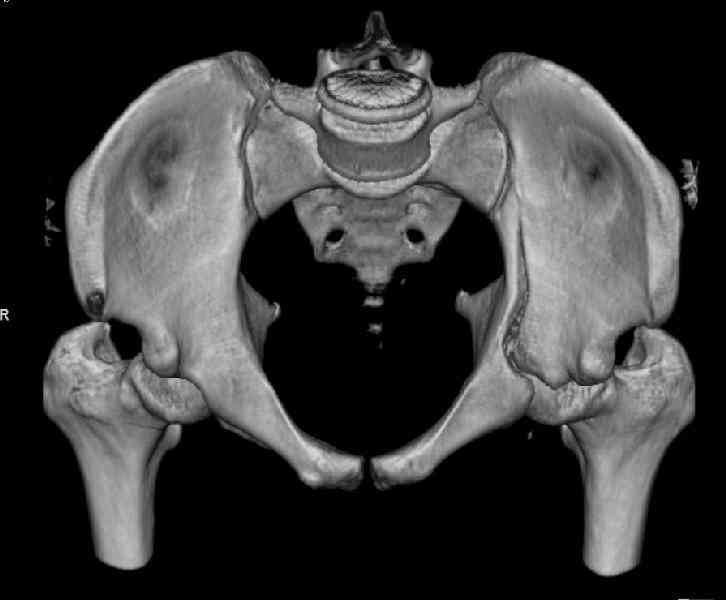

What is your indication for surgical management? What kind of fracture do you think it is? It looks like a transverse type although it has been a couple of years since I looked at an acetabular fracture.

The last two images from the 3-D CT scan certainly makes the fracture look worse than the plan radiographs.

The joint is non-concentric as the head appears to be either "following the caudal segment", or the dome component is displaced from the tethered head... or so it seems... and he's young... so, many fracture surgeons would recommend reduction and fixation.

Some more images. Does it help to guess which part of the acetabulum is displaced?